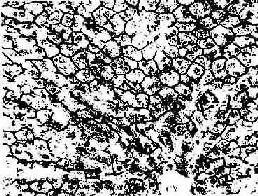

肝小叶(hepatic lobule)是肝的基本结构单位,呈多角棱柱体,长约2nm,宽约1mm ,成人肝约有50万~100万个肝小叶(图13-9)。小叶之间以少量结缔组织分隔,有的动物(如猪)的肝小叶分界明显,而人的肝小叶间结缔组织很少,相邻肝小叶常连成一片,分界不清(图13-10)。肝小叶中央有一条沿其长轴走行的中央静脉(central vein),中央静脉周围是大致呈放射状排列的肝细胞和肝血窦。

图13-9 肝小叶模式图

图13-10 肝小叶横切图